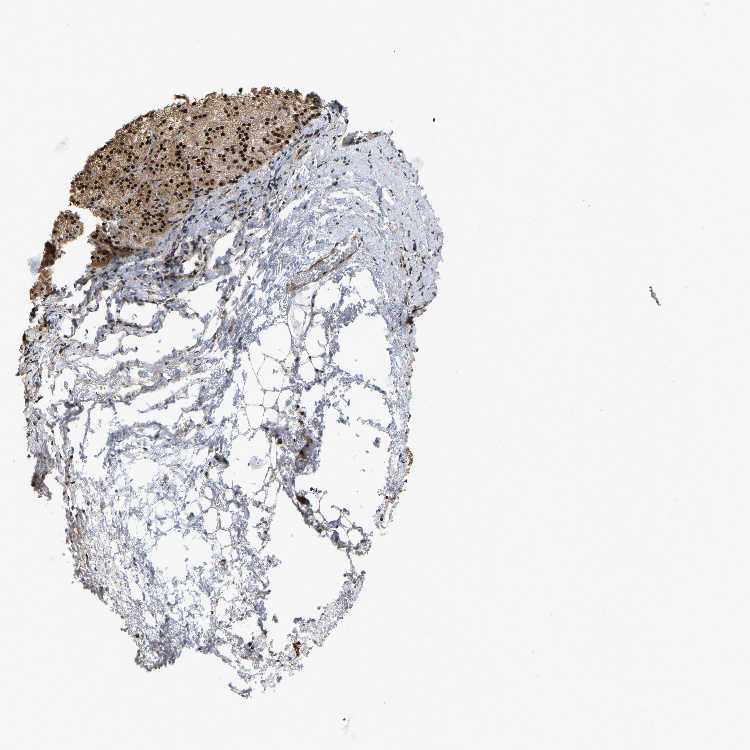

ADRENAL GLAND - Antibody stainingi

Antibody staining in the annotated cell types in the current human tissue is reported as not detected, low, medium, or high, based on conventional immunohistochemistry profiling in selected tissues. This score is based on the combination of the staining intensity and fraction of stained cells.

Each image is clickable and will lead to virtual microscopy that enables deeper exploration of all samples and also displays staining intensity scores, fraction scores and subcellular localization as well as patient and tissue information for each sample.

Antibody HPA017882

Glandular cells High